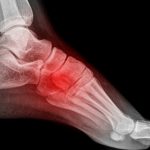

Depois de receber atendimento médico, você provavelmente fará um raio X para confirmar ou não a suspeita de fratura óssea. Logo após isso, se o osso quebrado for confirmado, o médico vai colocar uma tala ou um gesso no local lesionado.